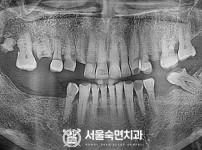

임플란트-전후사진1

치과를-선택할-때-꼭-확인하세요-서울숙면치과-임플란트-전후사진